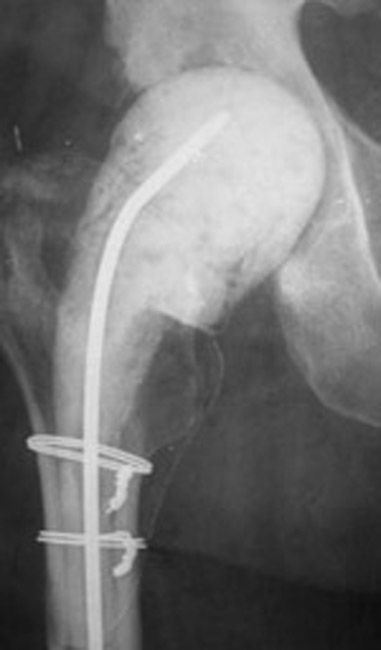

An antibiotic spacer in a hip joint

An antibiotic spacer in a hip joint.